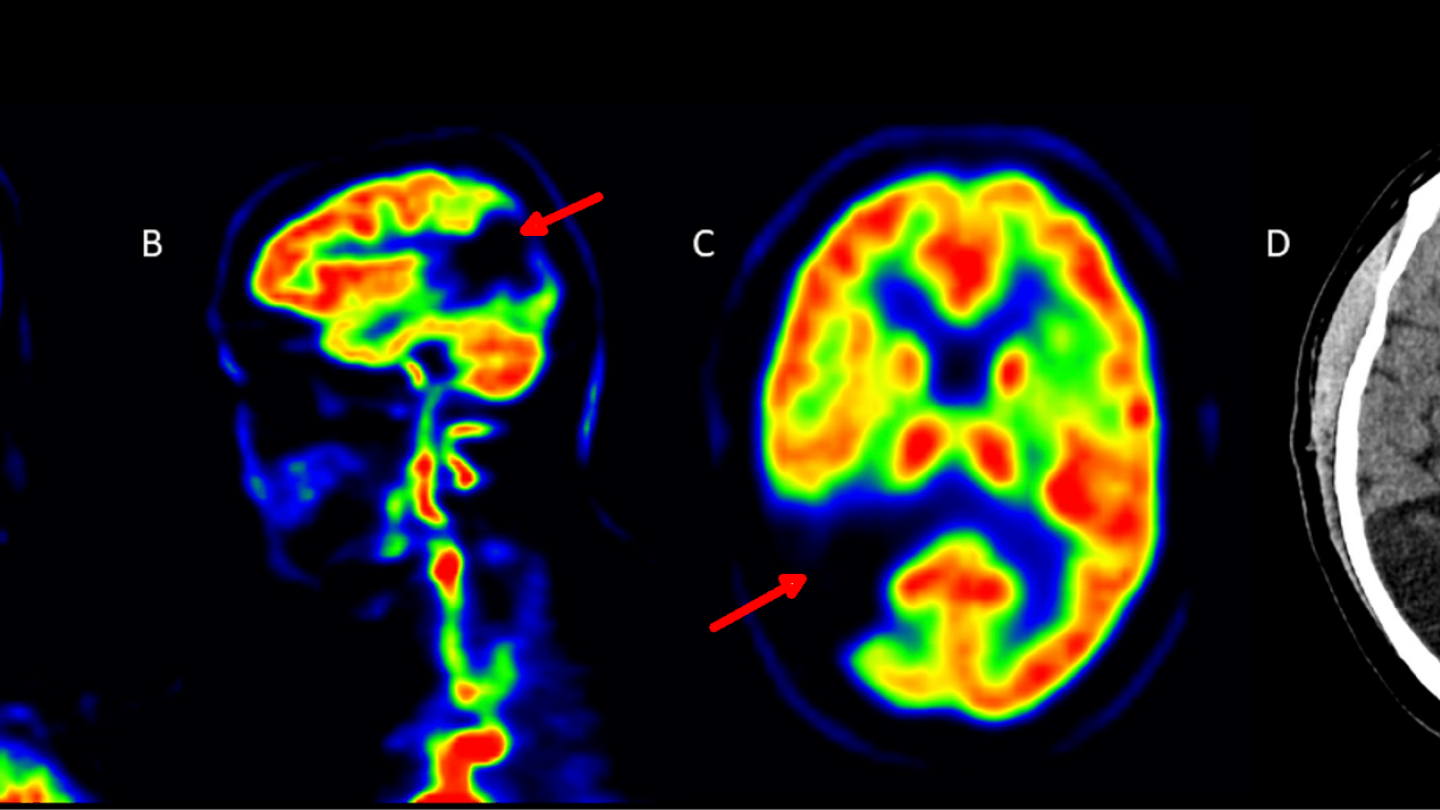

Oheisessa kuvassa on esimerkki yhdestä kuvatusta potilaasta. Kuvissa havaittiin selvä aivoinfarkti, joka ei ollut aiheuttanut potilaalle oireita eikä sitä ollut todettu aiemmin. Olemme havainneet muutoksia myös munuaisten verenvirtauksessa.

Aivoinfarkti näkyy nuolen osoittamissa paikoissa aivojen PET-kuvissa eri suunnista katsottuna. Oikeanpuoleisin kuva esittää vaurioalueen myös röntgentietokoneleikekuvassa.